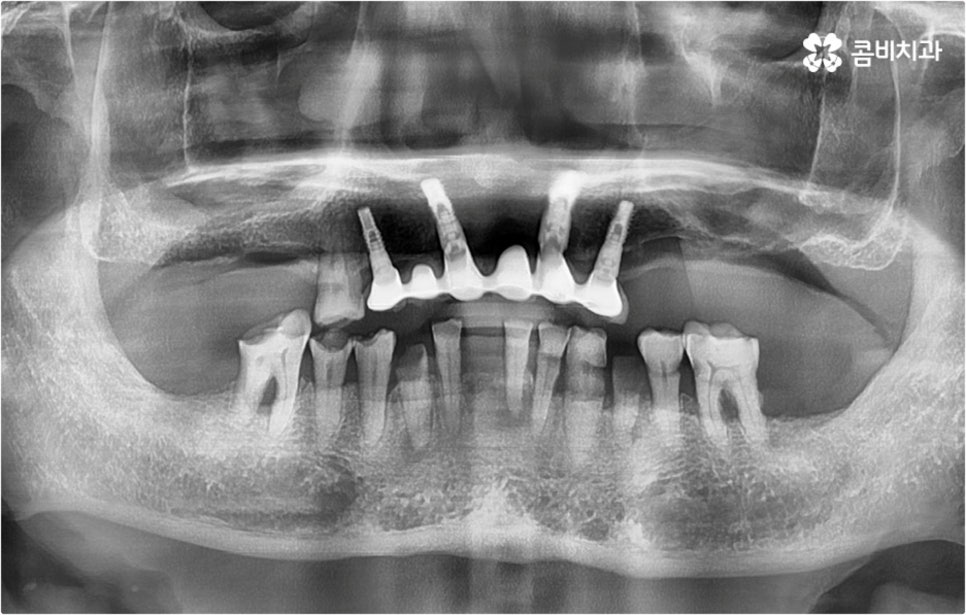

이때 환자분들의 상황에 따라서 임플란트 시술이 어려운 분들도 있을 수 있고 시술 전에 다른 치료를 선행해야 하는 분들도 있을 수 있기 때문에 먼저 꼼꼼하게 검진을 받아보실 필요가 있습니다. 특히 대다수의 치아를 잃어버리고 전악임플란트 를 진행하시는 분들의 경우 원인에 따라서 대처 방법이 다를 수 있는데요.

예를 들어 사고를 통해 한꺼번에 여러 개의 치아가 부러지거나 빠진 경우 연령 또는 전신 질환 여부 등을 살펴보고 치조골 상태가 양호하다면 보다 빠르고 간편한 당일 식립 방식을 이용해 볼 수 있어요. 그러나 하나 둘씩 치아가 빠질 때 마다 제때 치료를 해 주지 않아 치료 시기를 놓치고 결과적으로 무치악 상태에 이른지 오래 된 경우 또는 틀니를 오래 착용하여 잇몸뼈가 이미 많이 내려앉은 경우라면 바탕이 되는 잇몸뼈를 보충해 준 후 식립을 진행하는 방식을 이용해야 할 거예요.

또한 상악동과의 거리가 짧다면 거상술을 선행해야 할 수도 있고 심각한 치주 질환이 원인이라면 이를 먼저 깨끗하게 치료해 준 후 식립을 진행해야 성공률 또는 지속률이 높아질 수 있어요.

아무 것도 없는 상태에서 제대로 저작 기능을 발휘할 수 있도록 다시 구강 내부를 재현하는 전악임플란트 는 굉장히 고난도에 속하는 치료이기 때문에 충분한 임상 경험을 가지고 있는 숙련된 의료진과 함께 하실 필요가 있어요. 전악임플란트 방식이 빠진 영구치 자리마다 다 임플란트를 식립하는 것이 아니라, 상하악 각각에 8~12개 정도로 필요한 최소한의 인공 치근을 심고 그 사이 사이는 브릿지 방식으로 보철물을 연결하는 것이기 때문에 저작력을 골고루 분담하여 안정적인 지속성을 높일 수 있도록 환자 개개인의 상태에 맞게 인공 치근의 위치, 각도, 간격, 심는 깊이 등을 세밀하게 설정하여 교합을 제대로 맞출 수 있는 시술자의 뛰어난 기술력과 풍부한 노하우가 요구되는 거예요.

또한 이를 위해서 치아 주변 조직과의 거리나 잇몸뼈 높이, 밀도 등을 정확하게 파악할 수 있도록 도와주는 3D CT와 같은 정밀 진단 장비를 갖추고 환자분들의 상황에 맞는 계획을 세워 무리하지 않게 진행할 수 있는 체계적인 시스템을 운용하는 치과에서 임플란트 시술을 받으실 필요가 있어요. 만약 치과내 자체 기공소를 갖추고 있다면 보철물 제작에 대한 피드백이 보다 빠르게 전달, 반영될 수 있어 환자분들이 이용하시기에 좀 더 편안하실 거예요.